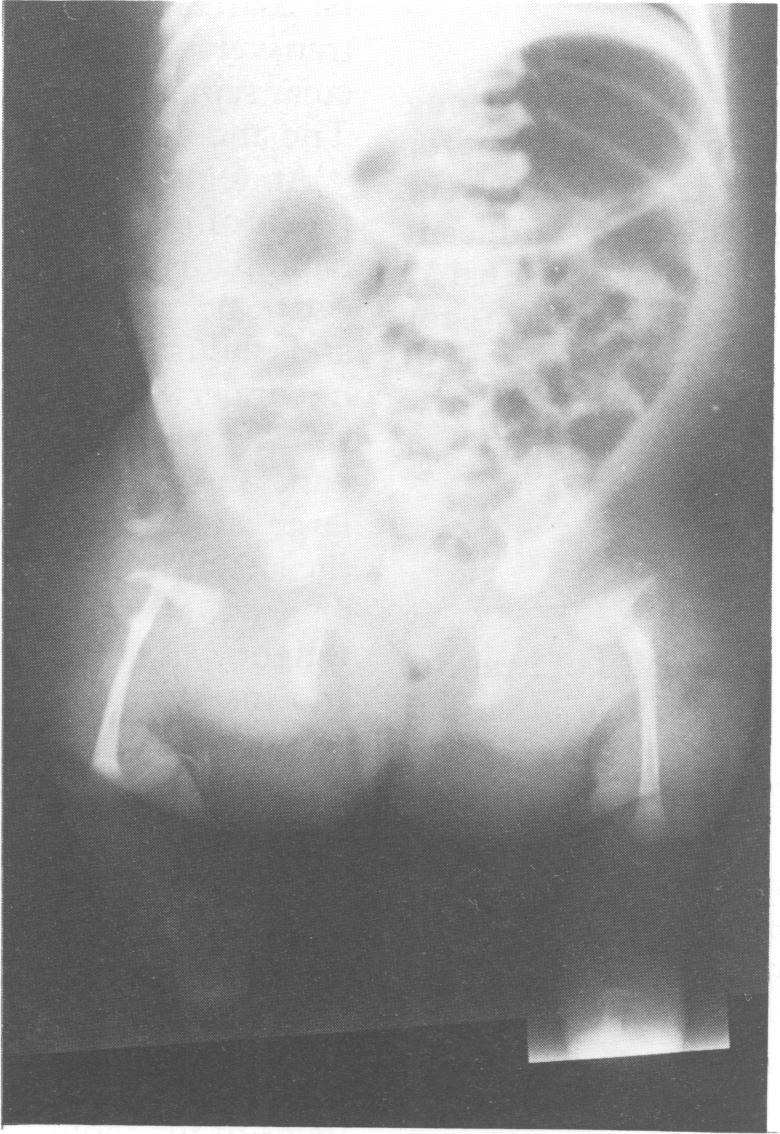

A third family with two Italian neonates affected with limb/pelvis-hypoplasia/aplasia syndrome is reported. The disorder shows autosomal recessive inheritance.

据报道,有第三个家庭的两名意大利新生儿患有肢体/骨盆发育不全/发育不全综合征。该疾病呈常染色体隐性遗传。